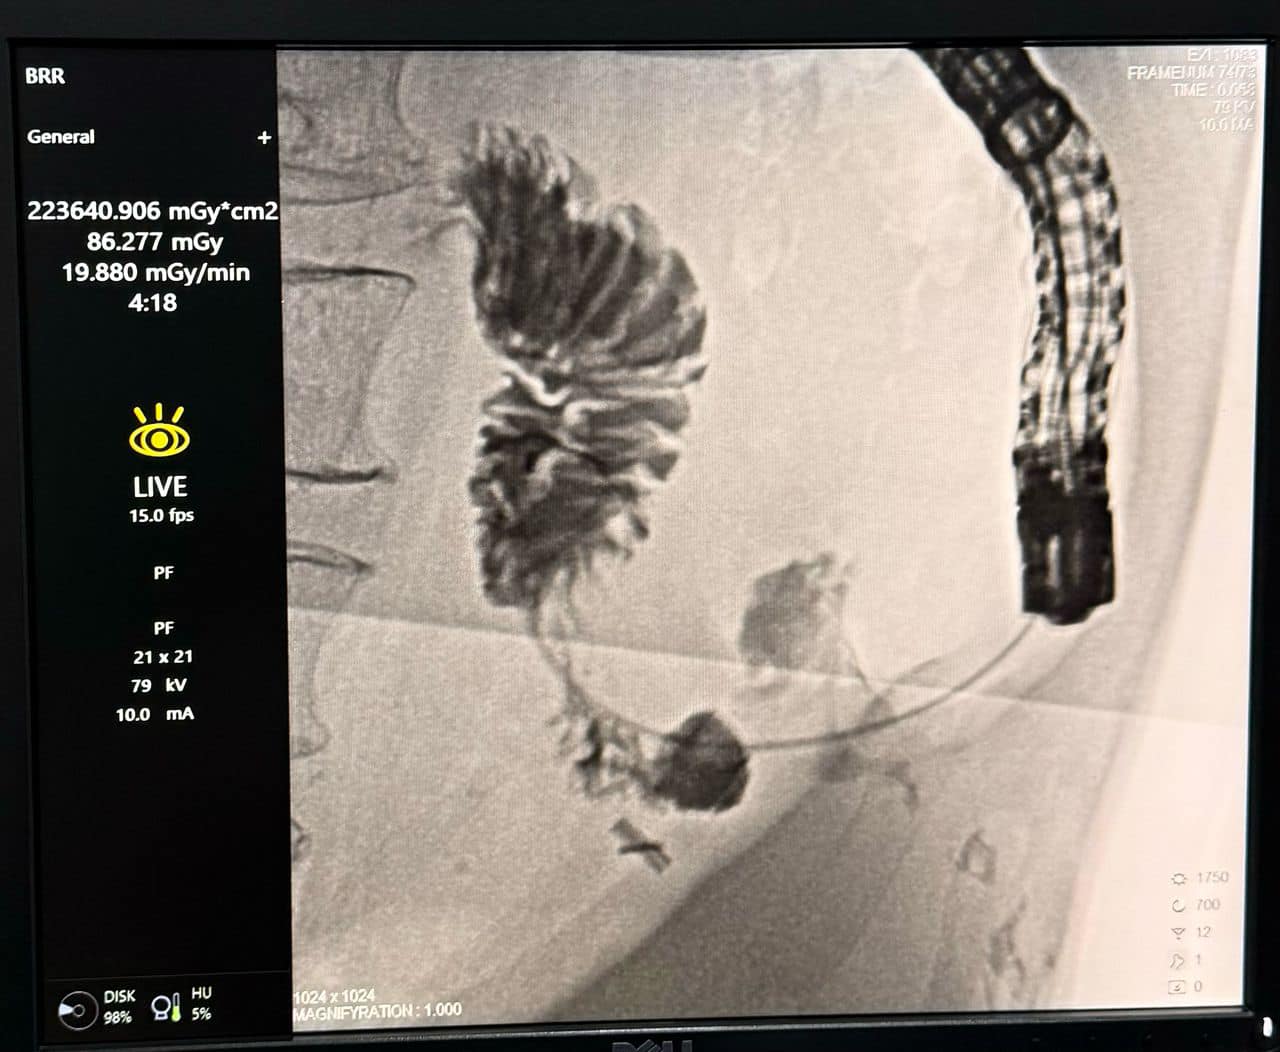

Операция была выполнена с использованием металлического стента SEMS (Self-Expandable Metal Stent), который обладает расширяющимися свойствами. Это способствовало нормализации пищевого тракта и улучшению состояния пациента.

«Операция была выполнена с использованием эндоскопии и рентгеноскопии, строго в соответствии с международными стандартами минимально инвазивной хирургии. Благодаря современному оборудованию и стентам мы смогли значительно улучшить качество жизни пациента», — подчеркнул Мусоев.